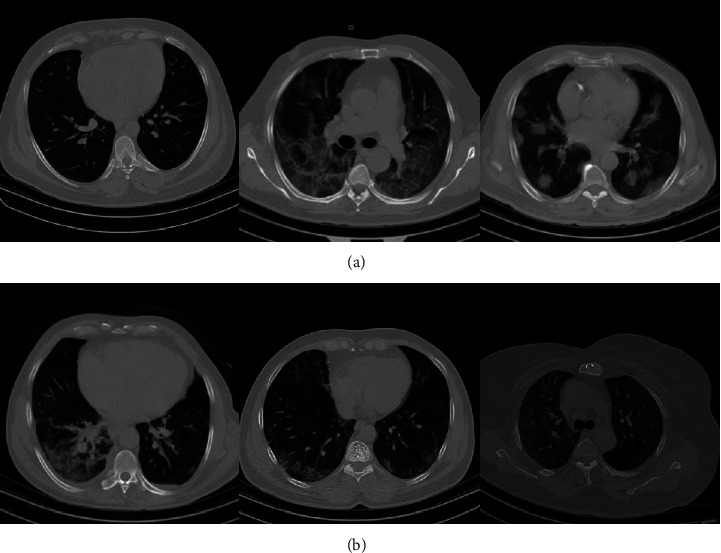

The dataset collection includes chest CT scan images. COVID-19 infected and noninfected or healthy are the two classes into which the data is divided. The CT scan images of COVID-19 patients admitted with a definitive diagnosis of COVID-19 and noninfected patients from June 1, 2021, to December 20, 2021, were extracted from the Picture Archiving and Communication system (PACS) in Ayatollah Taleghani Hospital of Abadan, Iran. The dataset consisted of 238 images. The number of healthy and COVID-19 infected images is equal to 108 and 130, respectively. There is no restriction on the selection of the disease variant, and images of all Covid-19's variants have been collected in this database. This study was approved by the ethical committee board of Abadan University of Medical Sciences (Ethics code: IR.ABADANUMS.REC.1399.207). Some chest Ct-scan examples of the collected database are shown in Figure 10.

Figure 10.

Some chest CT scan samples of the collected database in different scales, (a) covid-19 patients and (b) noncovid cases.